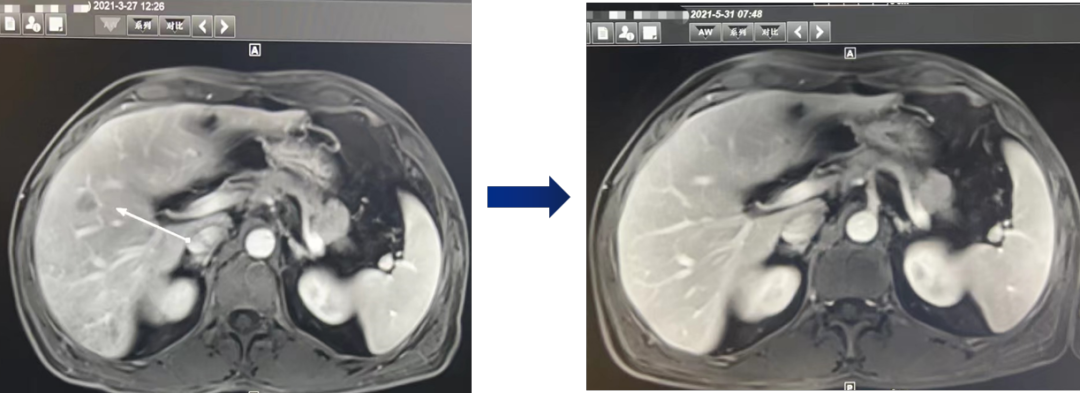

在全球,结直肠癌是发病率位居第三位、病死率位居第二位的肿瘤。肠镜筛查的普及以及手术方式的提升显著降低了结直肠癌的死亡率,但仍有一部分患者在初诊时已发展为晚期,失去手术根治的机会,且预后较差,5年生存率仅12%。许多转移性结直肠癌(mCRC)患者在经历一线治疗后,面临无药可用的困境。近年来,随着靶免联合治疗在系统治疗中逐渐前移,各种靶向治疗药物在mCRC的诊疗中也越发举足轻重。本文分享2例晚期结肠癌患者的诊疗经过,呈现瑞戈非尼在二线治疗为患者带来长生存的治疗价值及其良好的后线应用前景,以期为临床医生提供诊疗借鉴。 病例提供:海军军医大学附属长征医院 王湛 王湛 病例基本情况 一般信息:女 ,58岁。2020年10月,患者无明显诱因出现腹胀,无伴随症状,未予重视。后腹胀进行性加重,2020年11月中旬下腹部隐痛,与进食及体位变化无关,无肩背部放射痛。 辅助检查: 腹部超声:腹腔积液。 腹水脱落细胞病理:腺癌。 腹部增强CT:结肠肝曲癌;腹盆腔积液,腹盆腔腹膜多发转移。 结肠镜(2020-12-4):升结肠近肝曲见隆起型新生物,范围约4cm,新生物表面分叶状,质脆,触之易出血。肠腔狭窄,内镜尚可通过。 2020-12-8病理:横结肠,中分化腺癌,含部分粘液腺癌。 一线治疗2020-12-03至2021-02-24 CAPEOX+贝伐珠单抗 治疗4周期 病情进展,腹胀、腹痛加重,腹水增加。 2021-3-31 PET-CT:腹腔内及腹膜、脾脏、纵隔及右侧心膈角区、左侧锁骨区多发代谢增高灶,结合病史,考虑转移;双肺转移;腹腔及盆腔积液;结肠显示欠清,请结合肠镜检查;双侧胸腔少量积液,左肺下叶部分不张;双肺少许慢性炎症;右肝血管瘤;左肾结石。;子宫术后,痔疮可能;脊柱退变,腰3不稳,腰3/4、4/5、腰5/骶1椎间盘突出。 PFS:3个月 2021-4-6,完善基因检测(腹水标本):KRAS/APC/TERT/TP53/ target=_blank class=infotextkey>P53 突变,TMB 7.98/Mb,MSS 二线治疗,2021-04-02至2021-12 2021-3-31 2021-6-2 2021-8-6肠镜:结肠镜顺利插至回盲部,回盲瓣呈唇状。结直肠粘膜呈桔红色,光滑湿润,有光泽。血管纹理呈树枝状,清晰可见。 PFS:8月 三线治疗,2021-12-13至2022-01-23 三氧化二砷 2021-6-2 2021-11-22 2021-11-22 2022-2-8 PFS:2月 四线治疗,2022-02-10 化疗+免疫+瑞戈非尼+三氧化二砷 2022-2-10开始使用小剂量化疗(雷替曲塞+奥沙利铂+伊立替康)+免疫(信迪利单抗)+瑞戈非尼+三氧化二砷治疗。 疗效评估(2022-9-20):患者病情再次取得缓解。 2022-9-22至今采用维持治疗,降低治疗强度:雷替曲塞 +信迪利单抗+瑞戈非尼+三氧化二砷 2022-9-20 2023-2-8 PFS:13个月+ 该患者为中年女性,诊断为晚期多发转移性结肠癌,基因检测提示KRAS突变,BRAF、NRAS野生型,微卫星稳定,无法进行根治性切除。一线治疗加予CAPEOX联合贝伐珠单抗,治疗4周期后出现病情进展,腹胀、腹痛加重,腹腔积液增加,二线采用瑞戈非尼联合免疫和化疗,患者耐受良好,1周期后腹胀明显缓解,全身状态、PET-CT、肠镜结果较之前明显改善,继续原方案治疗,PFS长达8月。二线治疗进展后完善基因检测,发现TP53 突变,经与患者充分沟通,三线治疗采用三氧化二砷,疗效不佳。四线治疗在三氧化二砷基础上加用瑞戈非尼+免疫+化疗,患者病情再次取得缓解,PFS 超过13个月。近年来,随着精准医学及靶向、免疫治疗的发展,mCRC的管理与治疗策略的制定也变得复杂,合理选择治疗手段、优化全程管理至关重要。本例患者经历了一线化疗联合免疫治疗后疾病出现快速进展,我们个体化地在二线治疗中应用瑞戈非尼联合方案,患者疾病得到控制,PFS 8个月。在四线治疗方案中,再次挑战瑞戈非尼,依然获得较好的疾病控制效果,目前PFS已超过13个月。基于CORRECT和CONCUR研究,瑞戈非尼用于mCRC三线治疗已积累大量临床数据,目前已成为mCRC三线标准治疗方案。此外,REGONIVO、REGOTORI以及RIN方案证实了瑞戈非尼联合免疫治疗MSS型肠癌取得更长的总生存期。一线治疗后疾病进展,能否将瑞戈非尼使用前移,在二线治疗中加用以进一步延长患者生存,以及前线已经暴露过瑞戈非尼,后线再次使用瑞戈非尼是否可行,仍待在临床研究中进一步证实。 02 病例分享二 病例提供:海军军医大学第一附属医院 王薇 王薇 病例基本情况 一般信息:男性,41岁。2020年10月8日,无明显诱因下出现便血,为鲜红色,伴肛门坠胀不适,无排便习惯改变,无腹胀,无消瘦。1997年因“胃溃疡”行胃部幽门切除术;2019年行混合痔手术。 辅助检查: CEA 3.4ng/ml,CA199 3.52u/ml。 当地医院肠镜(2020-11-20):(距肛缘8-10cm)可见粘膜不规则隆起,表面溃烂,易出血。 肠镜活检病理:(直肠)中分化腺癌。 盆腔MRI增强(2020-11-26):直肠中段癌,考虑mrT3N1Mx,MRF-,EMVI-。 肝脏MRI增强(2020-11-27):未见明显异常。 治疗经过 首次手术治疗2020-12-09 腹腔镜辅助直肠癌拖出式适形切除术+末端回肠造口术 术中探查:直肠下段肿物,质硬,未浸润浆膜层,周围系膜未见肿大淋巴结。肿瘤大小约4*4*2cm,占肠腔1/2周,系膜完整。 术后病理: 直肠溃疡型肿瘤大小4.5x3.5x1.5cm;中至低分化腺癌,部分为粘膜腺癌;浸润至外膜层; 癌结节( 3枚+)、脉管癌栓(+)、神经侵犯(+)、肿瘤出芽(+,PDC1级);上下切缘(-)、环周切缘(-)、吻合圈(-);周围淋巴结(2/6),直肠外膜淋巴结(2/4),最高群淋巴结(0/4); 基因分型:KRAS Exon-2 G12D突变,NRAS、BRAF、PIK3野生型;免疫组化:MSH2(+),MSH6(+),MLH1 (+),PMS2(+),pMMR;Ki-67 80%。 术后分期:pT3N2aMx IIIB期 术后辅助治疗(XELOX方案) XELOX方案化疗3周期; 拟行盆腔放疗50gy/25次,2021-03-25起放疗6次 术后复查 肝脏MRI增强(2021-03-27):肝脏多发结节,较前为新发,考虑肝内多发转移瘤 一线治疗,2021-04-22至2021-06-24 mXELIRI+贝伐珠单抗 治疗4周期 患者治疗后出现恶心呕吐,胃纳明显减退,Ⅱ°粒细胞下降,腹泻,脱发,轻度手足皮肤反应,手足冰凉,心悸。患者无法耐受继续治疗 维持治疗,2021-7-15至2021-8-26,卡培他滨+贝伐珠单抗,共计治疗3周期 肝脏MRI增强(2021-5-31、2021-8-24):肝右后叶上段7mm小结节灶,转移不除外,腹膜后稍大淋巴结较前相仿,随访。 2021-3-27与2021-5-31的肝脏MRI增强对比图 2021-8-24 肝脏MRI增强 盆腔MRI增强(2021-8-25):术区及骶前软组织肿胀,左侧条索影,结合CT考虑术区置管术后改变,较2021-06-01片大致相仿。 疗效评估:PR 后患者诉心悸、乏力、胃纳不佳;血压正常;心肌酶正常;心脏彩超LVEF 64%;EKG: 窦性心率,T波低平;尿蛋白(-)。患者对化疗非常抗拒。 二线治疗,2021-09-17至2021-12-15 盆腔MRI增强(2022-9-13):术区及骶前软组织肿胀,左侧条索影,结合CT考虑术区置管术后改变,较前片大致相仿。 胸部CT(2022-9-13): 右肺下小结节,随访。 疗效评估:PR。 2022-12-20肝脏MRI增强:平扫+增强未见明显异常。 2022-12-21盆腔MRI增强:直肠癌术后,盆腔区未见明显复发及转移病灶。 病例总结 该患者为中年男性,诊断为局部晚期直肠癌,原发灶术后分期IIIB期,基因检测KRASExon-2G12D突变、微卫星稳定。术后仅3月余在XELOX方案辅助化疗、盆腔放疗期间出现多发肝转移,疾病进展转移灶不可切除,进而接受XELIRI方案联合贝伐珠单抗二线全身治疗。治疗后肝脏多发转移瘤退缩理想,病灶明显缩小减少。但患者治疗副反应不可耐受,改卡培他滨联合贝伐单抗治疗后持续有效,但仍无法耐受副反应。遂予以瑞戈非尼靶向治疗:120mg日剂量口服,服用三周停用一周至今。患者耐受良好,近期复查未发现明显复发转移病灶。目前二线PFS已达23个月,瑞戈非尼二线维持治疗DoR17个月。目前,二线治疗在不同患者亚群的优选方案仍存在争议。而整个系统治疗到了三线阶段,标准治疗主要价值是能够延长患者的疾病控制时间,缩瘤效果和客观缓解率均不理想,并没有满足目前的治疗需求。根据目前的药物机制和临床研究结果,考虑到患者的具体情况:涵盖治疗目标、体质状况、对预估的不良事件的耐受性及是否存在相关危险因素、既往治疗用药情况等方面,我们采用了个体化的瑞戈非尼二线维持治疗方案取得良好疗效,这种治疗策略希望能在规范临床研究中证实。病例分享一